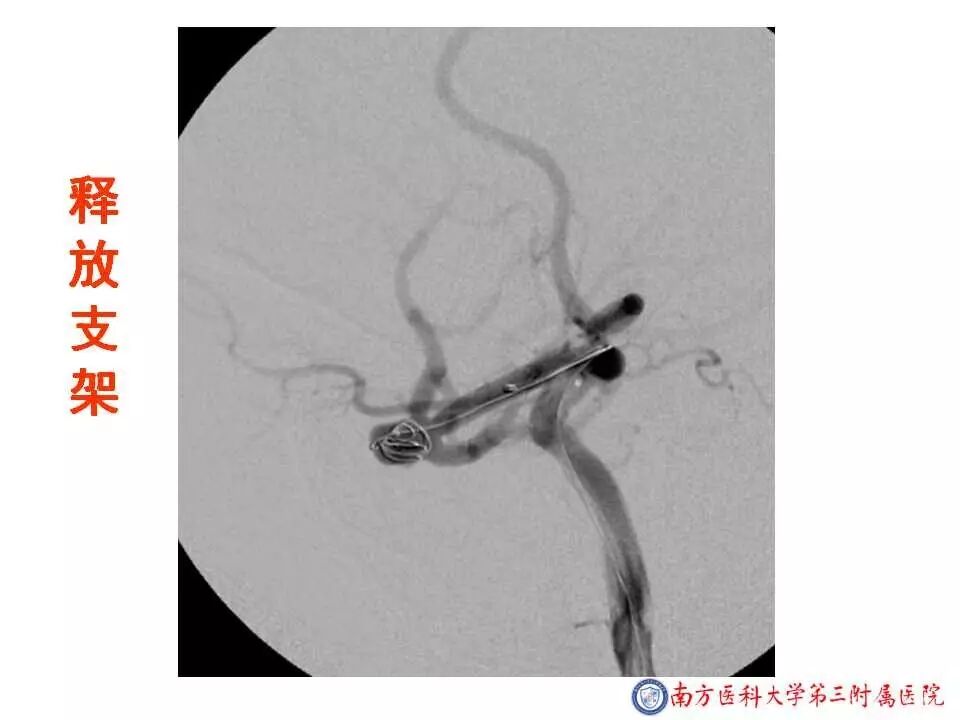

今天为大家分享的是“强生医疗CNV-神经介入专栏”第二十五期,由南方医科大学第三附属医院神经外科主任黄理金教授带来的“Enterprise支架辅助栓塞动脉瘤的优势”精彩讲课视频及PPT,欢迎观看。文章仅代表作者个人观点,如有不同见解,欢迎同道斧正!